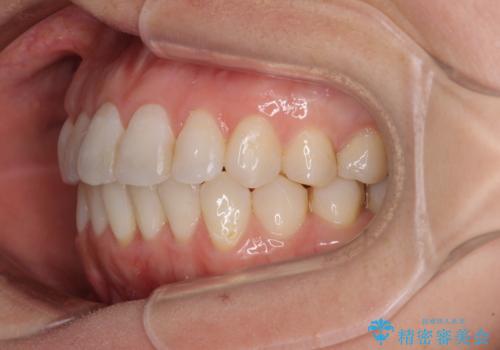

長年気にしていた前歯 インビザラインで目立たず改善

- ワイヤーではない矯正治療があると聞いたとのことで来院された患者様です。

長年前歯のデコボコを気にしていたもののワイヤー矯正に抵抗があり躊躇していたそうですが、インビザラインなら治療してみたいとのことで相談にいらっしゃいました。

インビザライン適用の歯列であったため、歯と歯の間を削るIPRを用いて改善することとしました。

下顎前歯の叢生が顕著な場合、歯列改善後に歯と歯と歯肉の間にブラックトライアングルという隙間ができてしまいます。

軽減することはできますが、完全に解決することは矯正治療のみでは不可能なため、リスクとして事前に周知しておく必要があります。